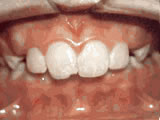

Crowding of the teeth

Patient started treatment at age 11 and wore braces for 26 months. He loves his new smile.